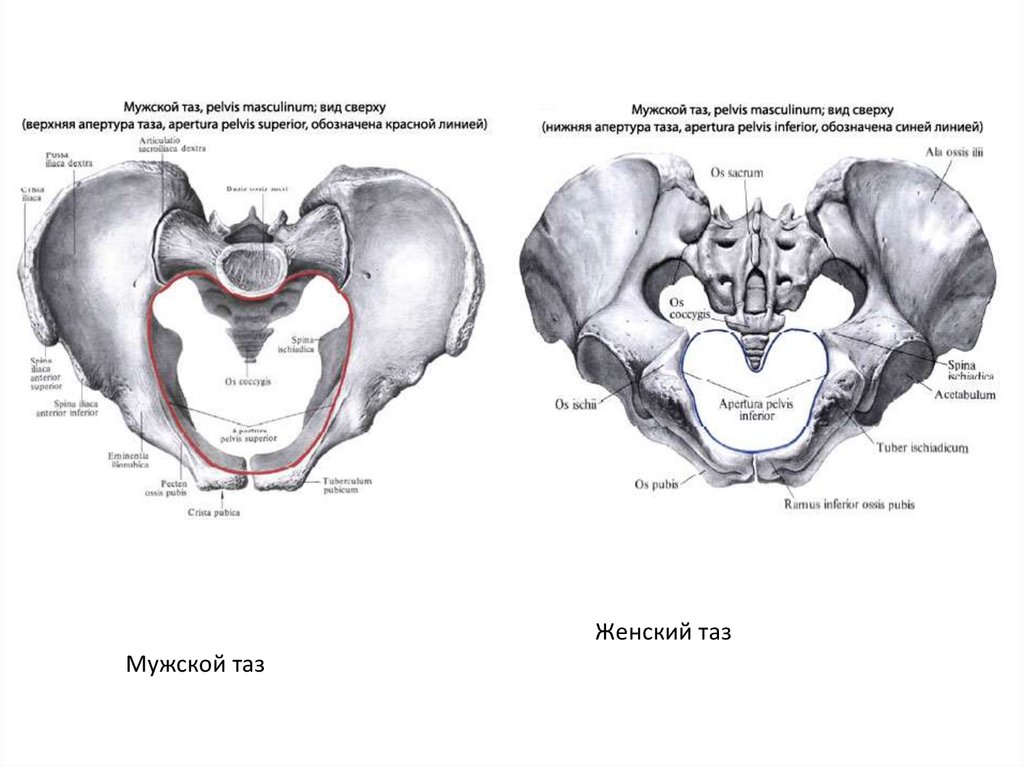

Анатомия малого таза: детальные схемы и изображения